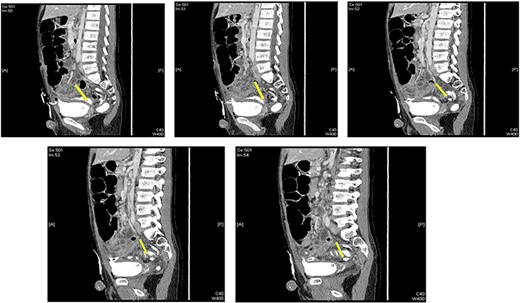

A CT cystography was performed, and it showed a vesicourachal diverticulum. The suprapubic drain that was placed intraoperatively was shown to be penetrating the diverticulum (Fig. 2). The urology department was consulted and the patient’s condition was discussed with his family. Management options were offered, including conservative management with Foley catheter placement and operative repair; the family opted for conservative management. The management included hourly monitoring of his urine output, antibiotic prophylaxis with intravenous cefuroxime 625 mg thrice a day and intravenous metronidazole 350 mg thrice a day, daily laboratory investigations (complete blood count, renal function tests and serum electrolytes), and a cystography performed after 7 days. The patient’s daily urine output is shown in Table1.

Multiple sagittal views showing the drain penetrating the urachus.